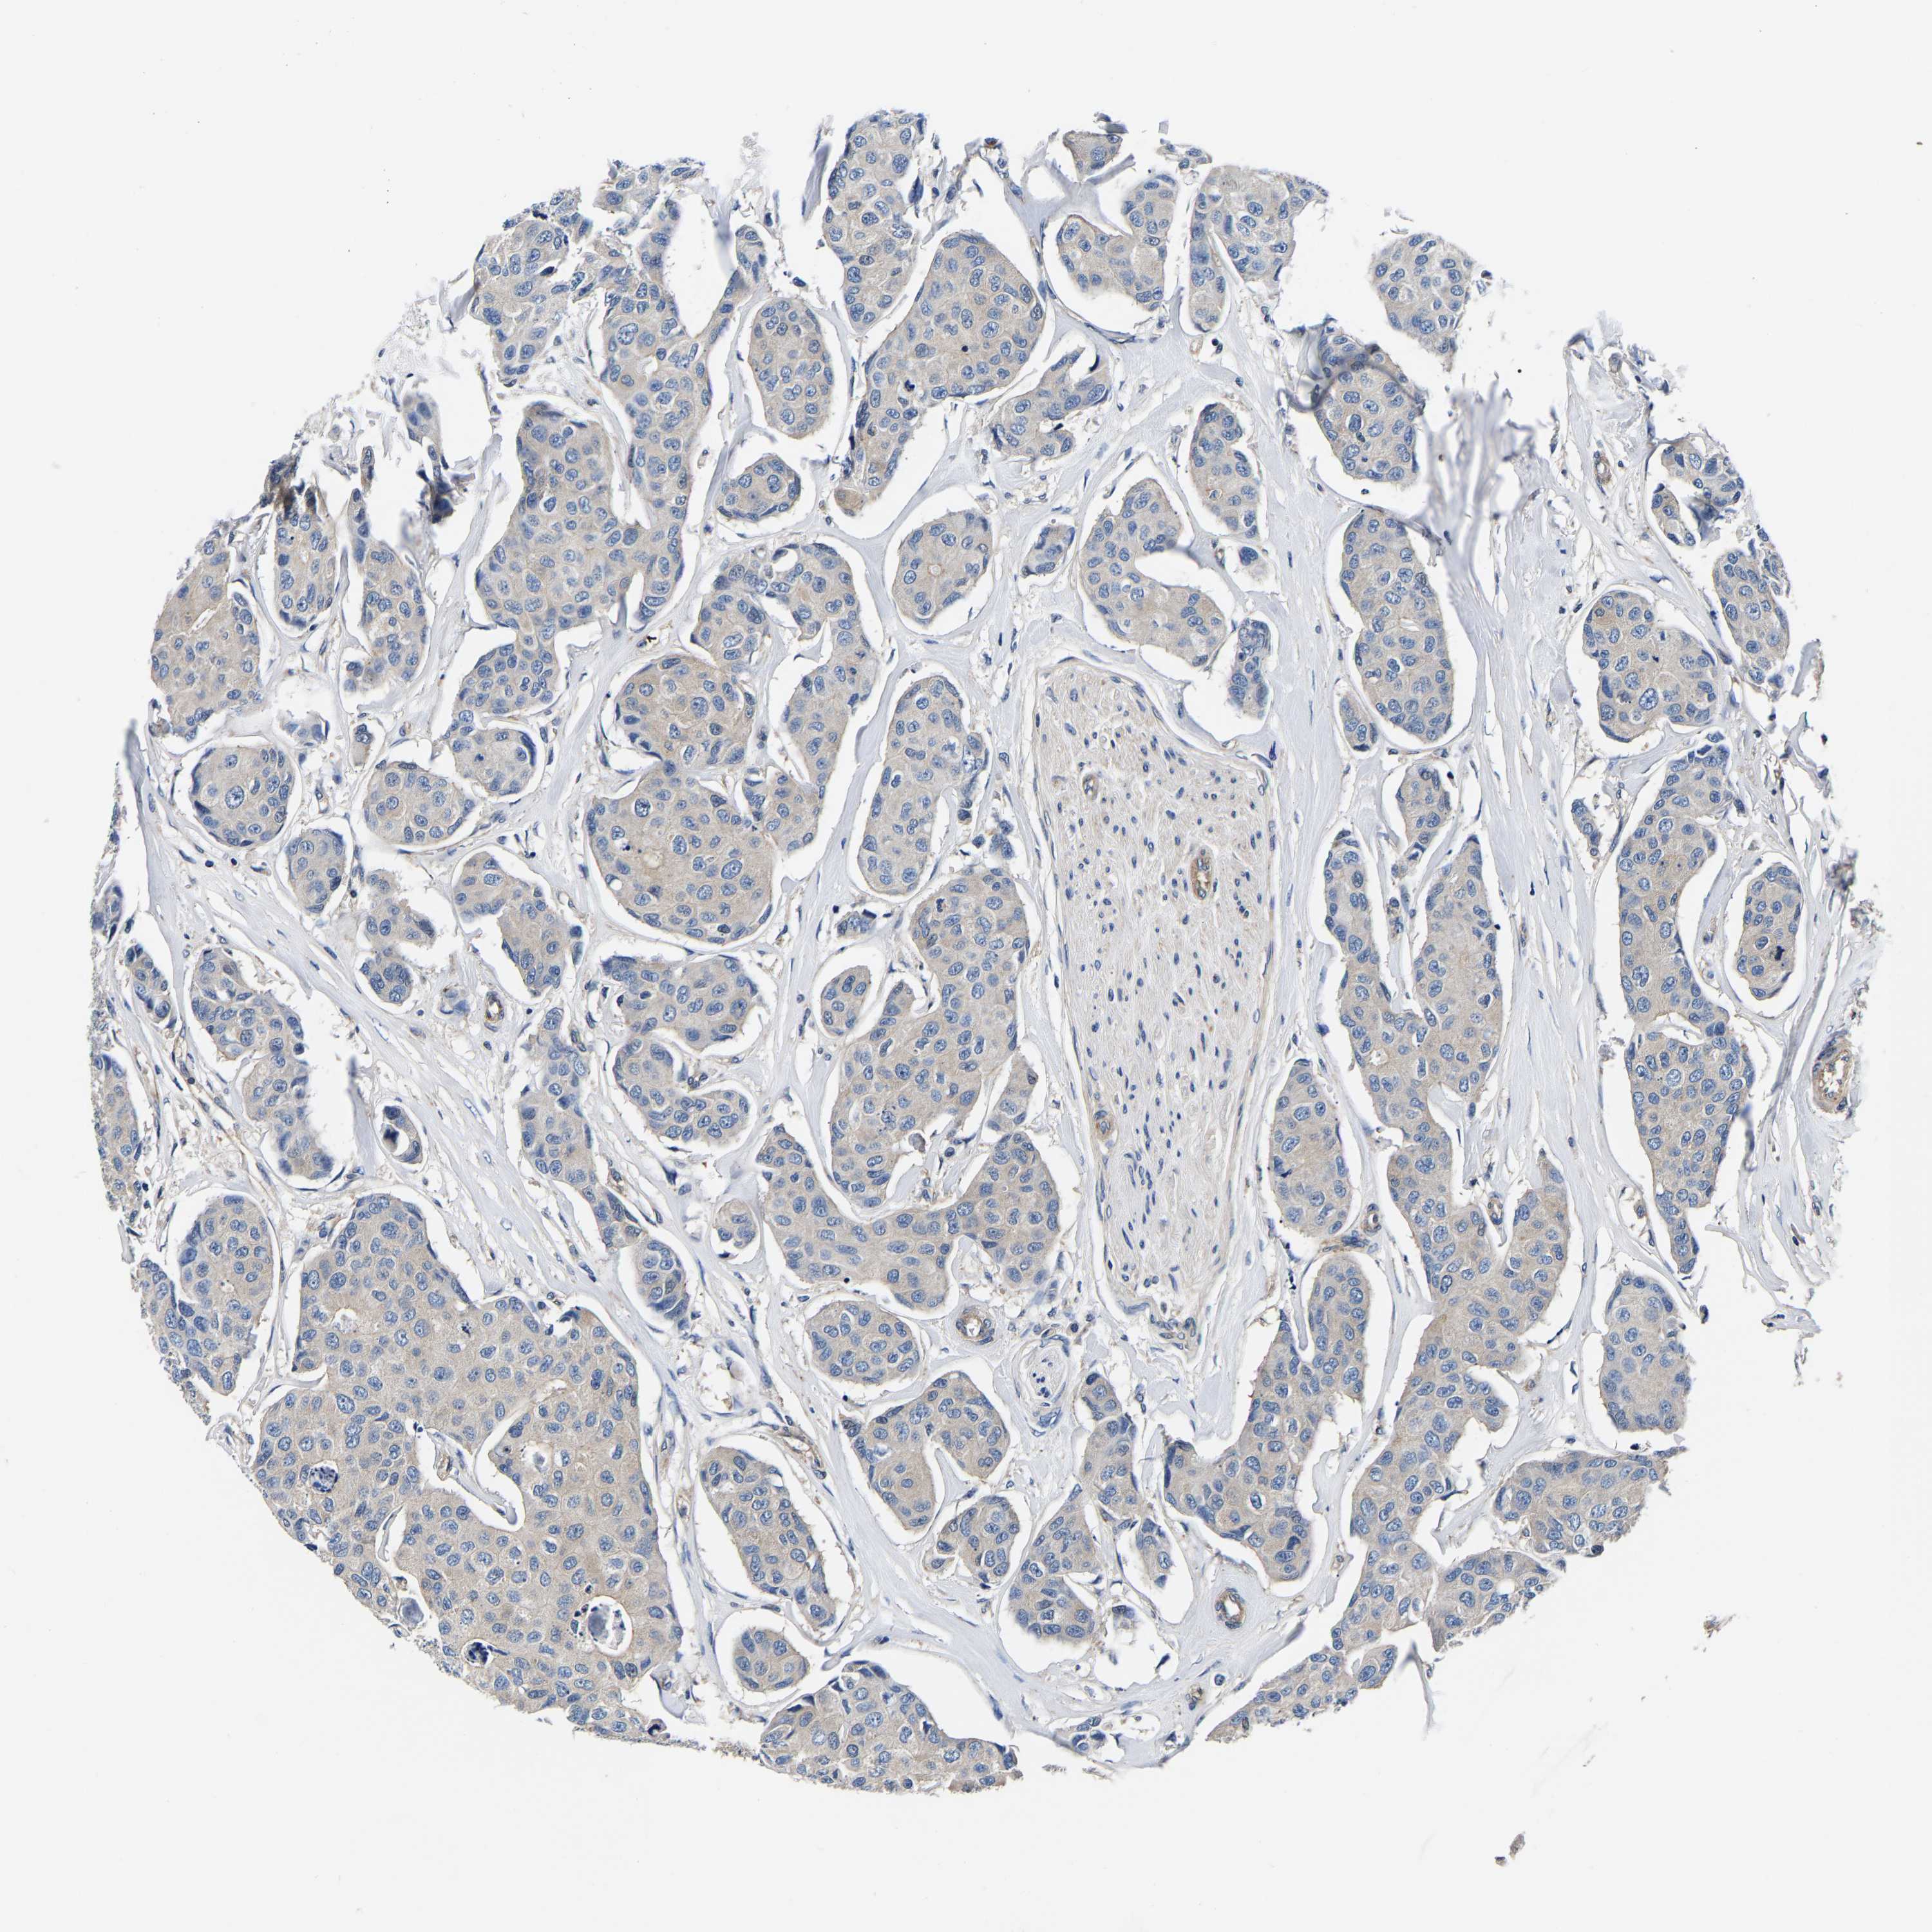

CANCER BREAST CANCER Show tissue menu

BRCA TCGA BRCA VALIDATION PROTEIN EXPRESSION